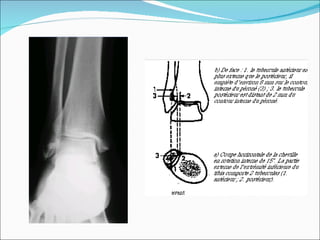

Calcanéus de face Incidence rétrotibiale ascendante  Sujet en décubitus dorsal, les deux membres inférieurs allongés sur la table, les pieds en flexion dorsale forcée, maintenus par une bande de traction, les talons sur la cassette disposés horizontalement. Le rayon directeur, incliné de 40° cranial, est centré au milieu du tiers postérieur de la plante du pied entre les malléoles. le cliché doit permettre une bonne visualisation des articulations talocalcanéennes et du calcanéus jusqu’à la petite apophyse. INCIDENCES COMPLÉMENTAIRES

Calcanéus de face Incidence rétrotibiale descendante Sujet debout, s’incline vers l’avant en prenant appui sur un support (dossier de chaise), les cuisses et les jambes légèrement fléchies, les pieds en flexion dorsale maximale, les talons joints sur la cassette. Le rayon directeur est incliné vers l’avant de 40° par rapport à la verticale et centré entre les bords postérosupérieurs du calcanéus. INCIDENCES COMPLÉMENTAIRES

Incidence: Sujet  debout  en appui bipodal sur un socle en bois.  Pied en légère  rotation interne. RD: parallèle à l’axe du 4éme métatarsien. Centrage 1 cm au dessus du plan d’appui. Distance du foyer film: 2m. Film appuyé contre la face postérieure de la jambe. Repère métallique : individualiser le point d’appui du talon Plan frontal

Plan frontal Incidence de Meary:  ajouter   surélévation de la cheville par un bloc. radiotransparant de 1 cm. Fil de plomb souple tendu en étrier entre les deux malléoles.

Moyens: Mesurer l’inclinaison de l’interligne tibio-talienne sur l’horizontale.  Déterminer la position de l’arrière pied par rapport au pilon tibial en traçant le trapèze d’appui de l’arrière pied 5°

Extrémité latérale  de la poulie talienne « e » Extrémité médiale  de la poulie talienne « i » Repère métallique latéral « E » Repère métallique médial « I » Milieu de la poulie talienne « m » Milieu de l’appui au sol « M »